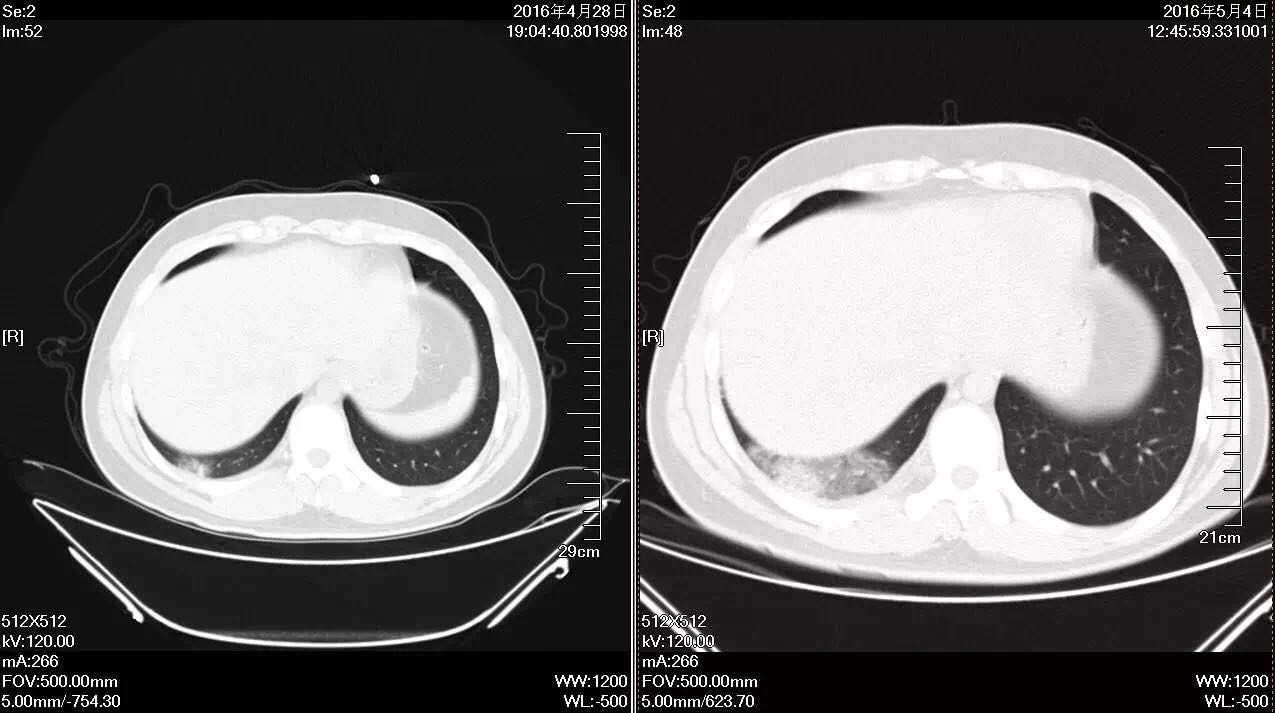

图1 入院查体T: 37.8 ℃,听诊右肺呼吸音低,未闻及干湿性啰音,心率68次/分。 诊断: 社区获得性肺炎,非重症 ; 2.胸膜炎; 3.胸腔积液。 病人青年男性,考虑抗感染力度不够、覆盖不足或结核可能,另外也考虑到我国支原体对阿奇霉素耐药率高的问题,给予磷霉素联合米诺环素抗感染,辅以止咳、化痰等治疗。病人于入院次日晨咳鲜红色血痰10ml,体温升至38.9℃,加用奥司他韦抗病毒,并予云南白药止血对症治疗。同时完善相关检查,降钙素原0.1ng/ml;血常规:WBC 10.78×109/L,C反应蛋白109.60mg/L;D-二聚体定量3.45ug/ml,我院正常值为0---0.5 ug/ml 白蛋白43.28g/L;血沉61.00mm/H; ANA谱及ANCA均未见异常;肺炎支原体抗体阴性;肺炎链球菌抗原定性阴性;24h痰液未找到抗酸杆菌。 此后病人发热、咯血无缓解,PPD试验阴性,行胸腔超声检查,报胸腔积液,液深1.8cm,建议胸腔穿刺、支气管镜检查进一步明确,病人家长均拒绝。考虑病人年少,无持续卧床史,双下肢无水肿,心电图无异常改变,D-二聚体升高考虑感染所致,加用头孢他啶进一步覆盖G-杆菌。病人体温峰值出现下降,咯血、胸痛仍无好转,入院第5天复查血常规:WBC 7.00×109/L,C反应蛋白149.16mg/L;D-二聚体定量3.95ug/ml;肌钙蛋白、BNP正常;血气分析示pH为7.52,PaO2为136mmHg,PaCO2为30.9mmHg(吸氧流量为2L/分);痰培养、血培养均为阴性。 再次评估病情,经较强抗感染治疗患者仍有发热、胸痛、咯血,D-二聚体较前升高,追问病史近期有夜间长时间端坐玩电脑诱因,考虑肺栓塞不能排除,停用云南白药。病人家长初拒绝CTPA检查,完善下肢血管超声未见异常,遂先行超声引导下胸腔穿刺,抽出不凝血,胸水常规:白细胞 1878×106/L,N80%,蛋白定性实验4+;胸水腺苷脱氨酶18.02U/L。再次与病人家长沟通后于入院第6天行CTPA检查,提示右下肺动脉栓塞,右肺片状影及胸腔积液均较前加重(见图2、3)。

图2

图3